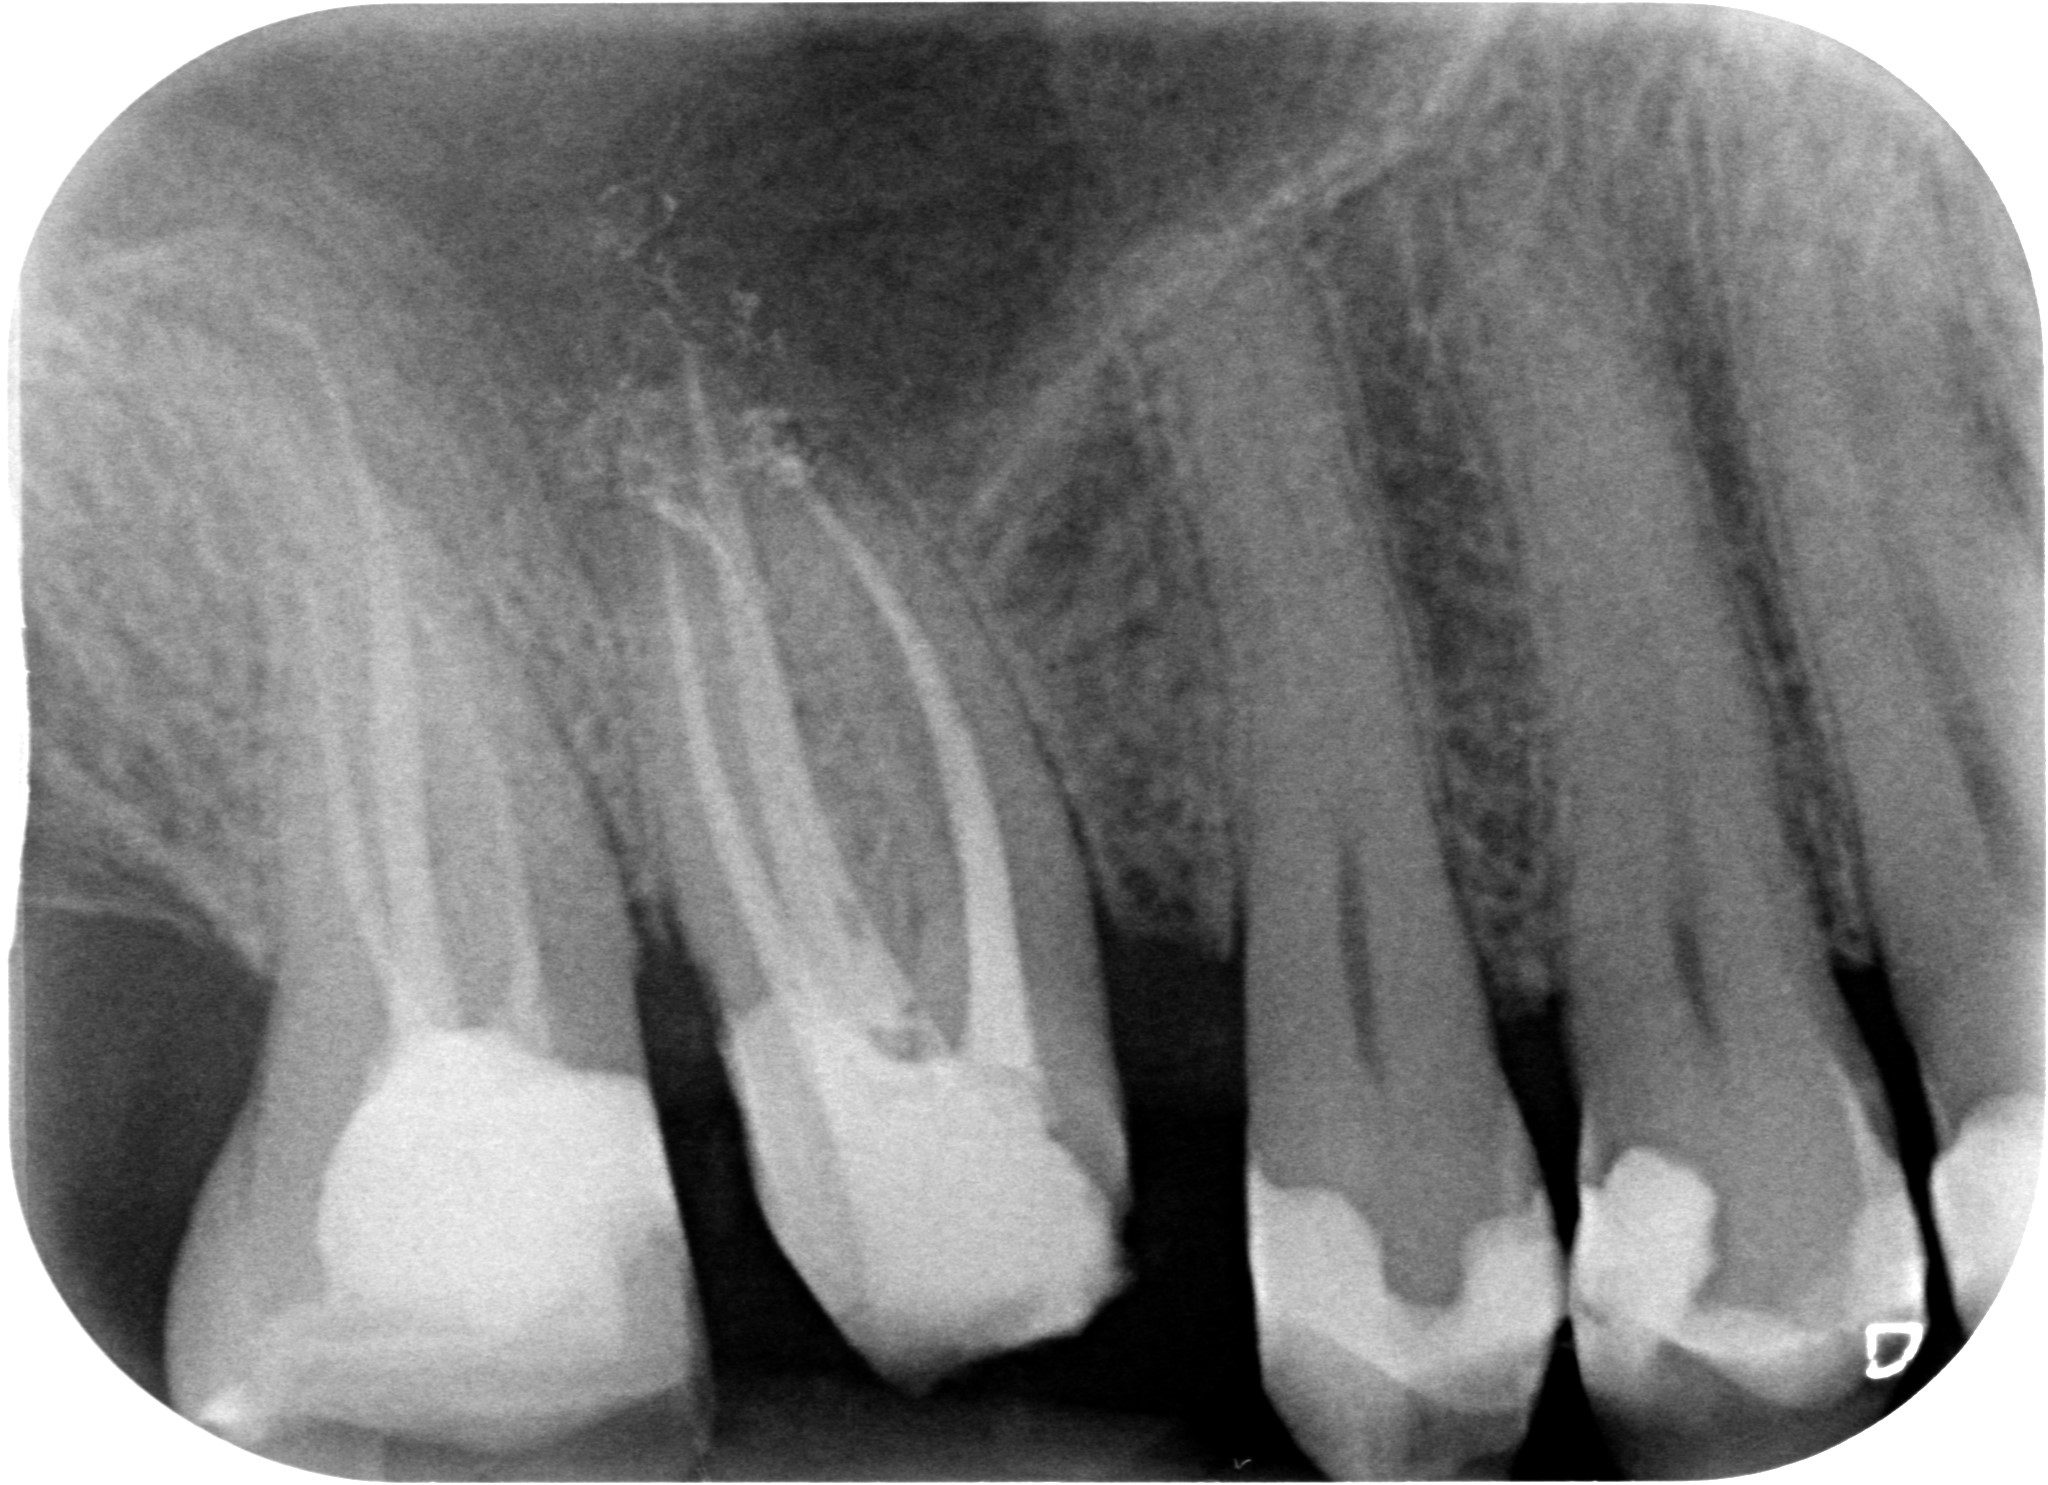

Allungamento di corona clinica 002

ESEGUIRE UN CORRETTO RITRATTAMENTO CANALARE ISOLANDO IL CAMPO CON LA DIGA DI GOMMA

Allungamento di corona clinica 003